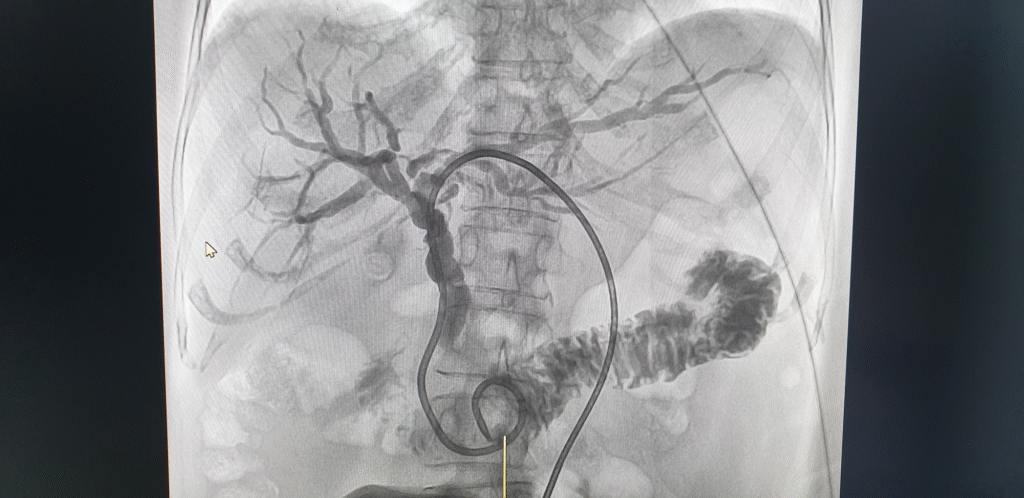

Percutaneous Transhepatic Biliary Drainage (PTBD) is a minimally invasive procedure performed by an Interventional Radiologist to relieve a blockage in your bile ducts.

- The Procedure: A small catheter (drainage tube) is inserted through the skin, across the liver, and into the blocked bile duct, using X-ray and ultrasound guidance. This catheter allows the bile to drain, either externally into a bag or internally into the intestine (with a subsequent procedure or catheter type).